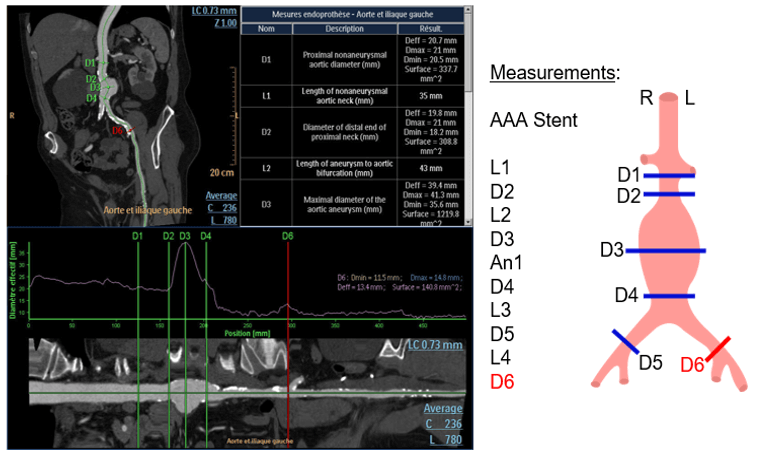

Endoprosthesis Planning

In this step, you can choose and import the type of prosthesis you want. To do so, you have only to click on the list of prosthesis models and select your choice.

Once the model is selected, you have to adjust the measurements as indicated on the template. For each measurement, check the light contour automatically created by the software.

Volume Rendering

Volume rendering (VR) will allow us to use predefined protocols to adjust the amount of opacity and color applied to the model. Then you can display the table of results referring to the necessary measurements for prosthesis fabrication.